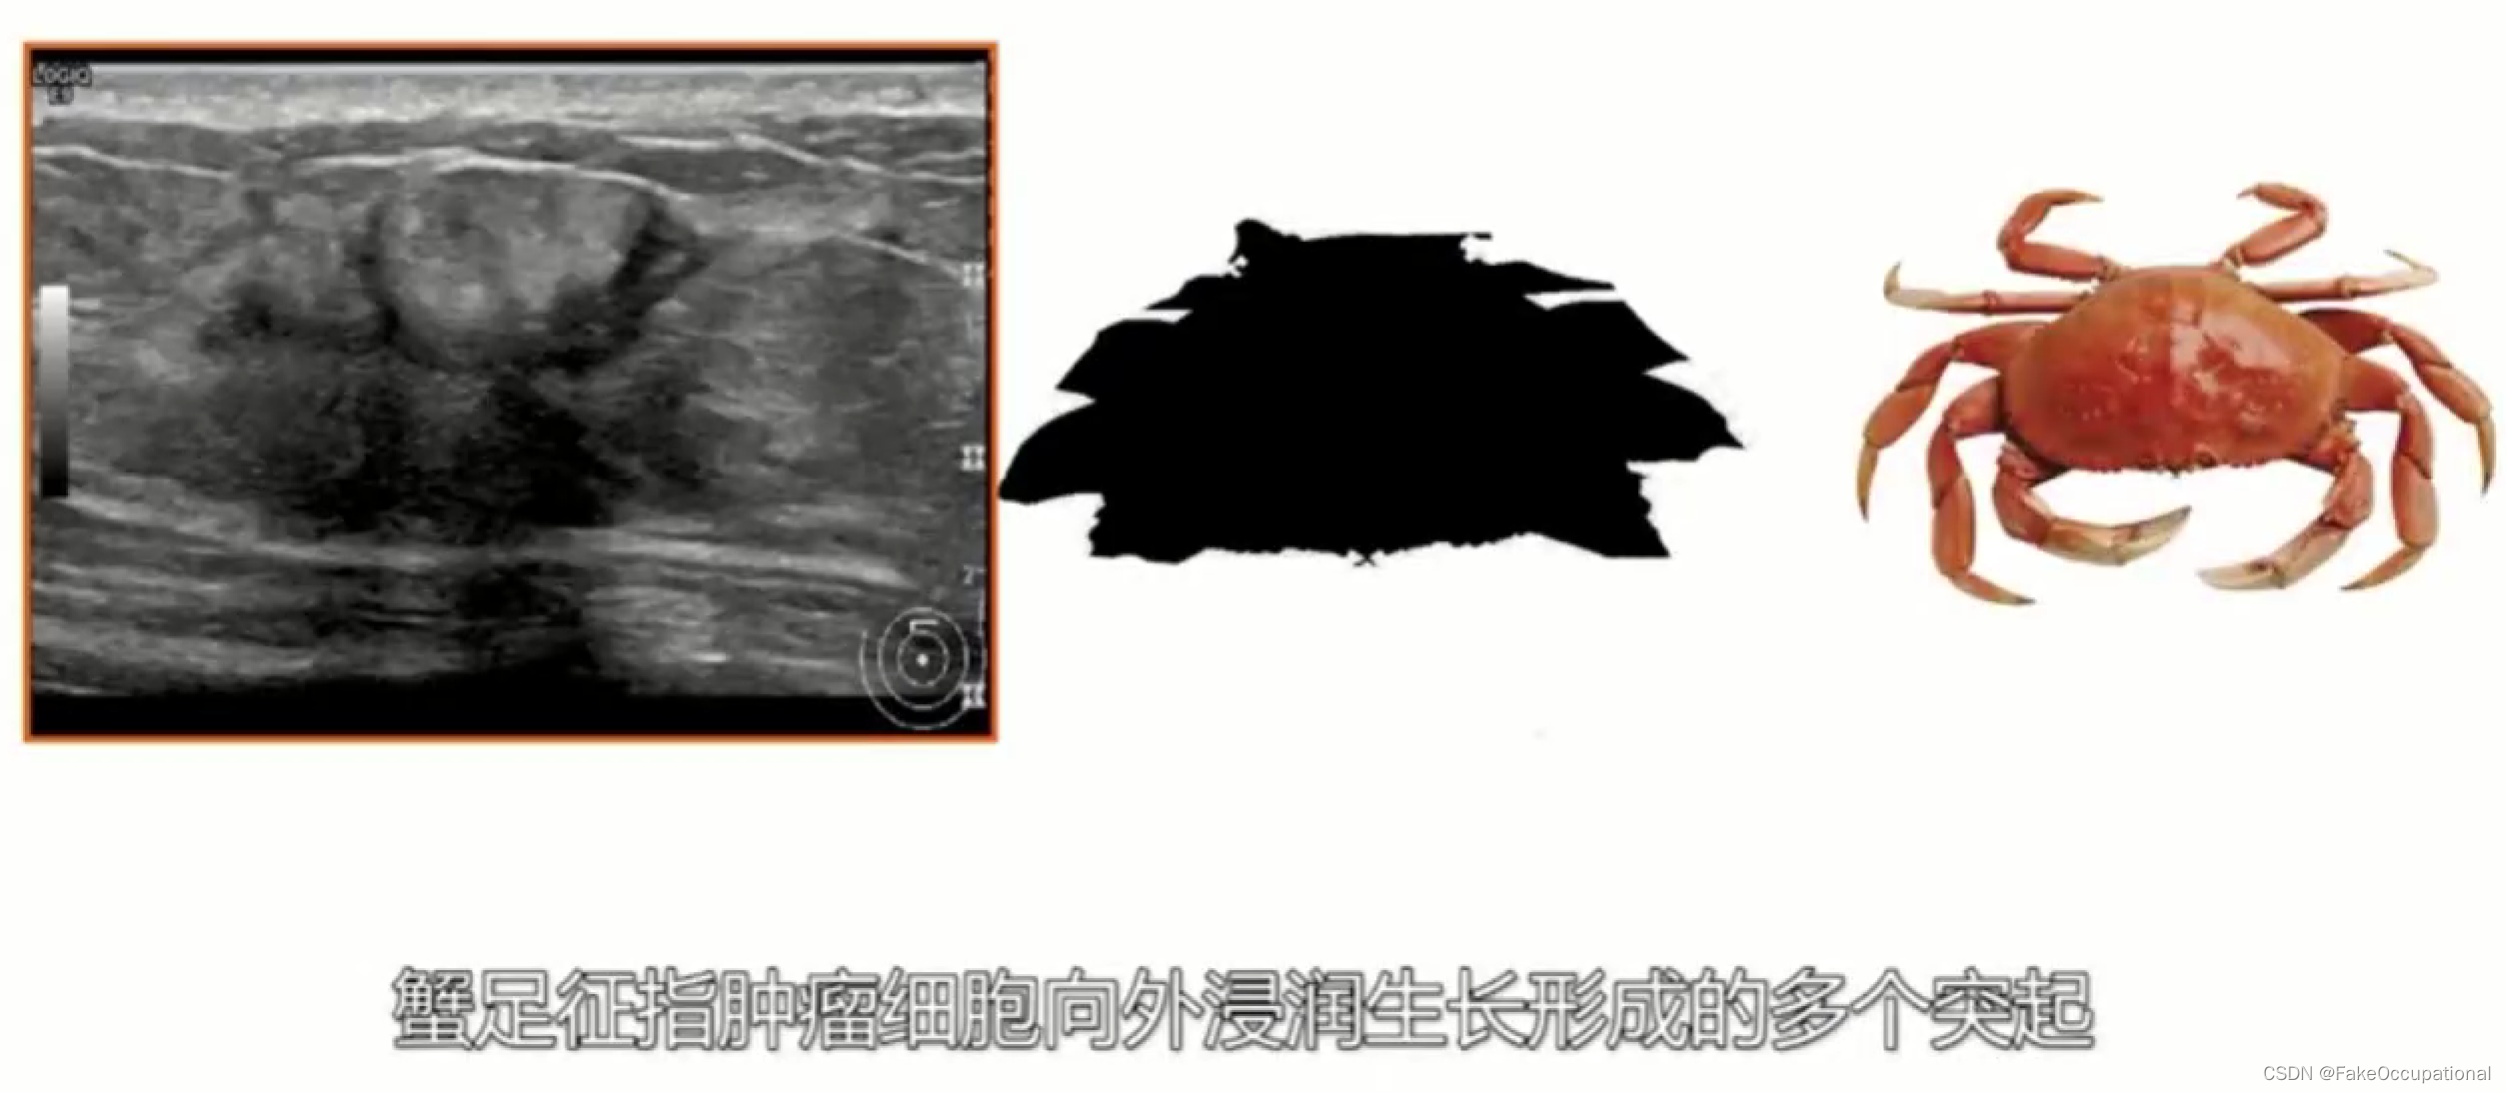

乳腺癌